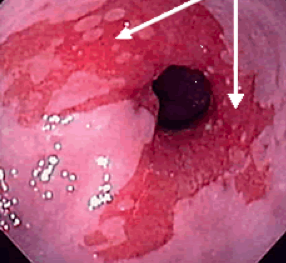

What is going on here?

What is the difference b/t these 2 images? Arrow?